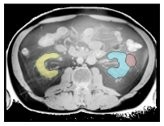

The COMFORT team has addressed this challenge by developing the MRSegmentator, which can automatically identify and outline 40 different body structures in MRI scans with high accuracy.